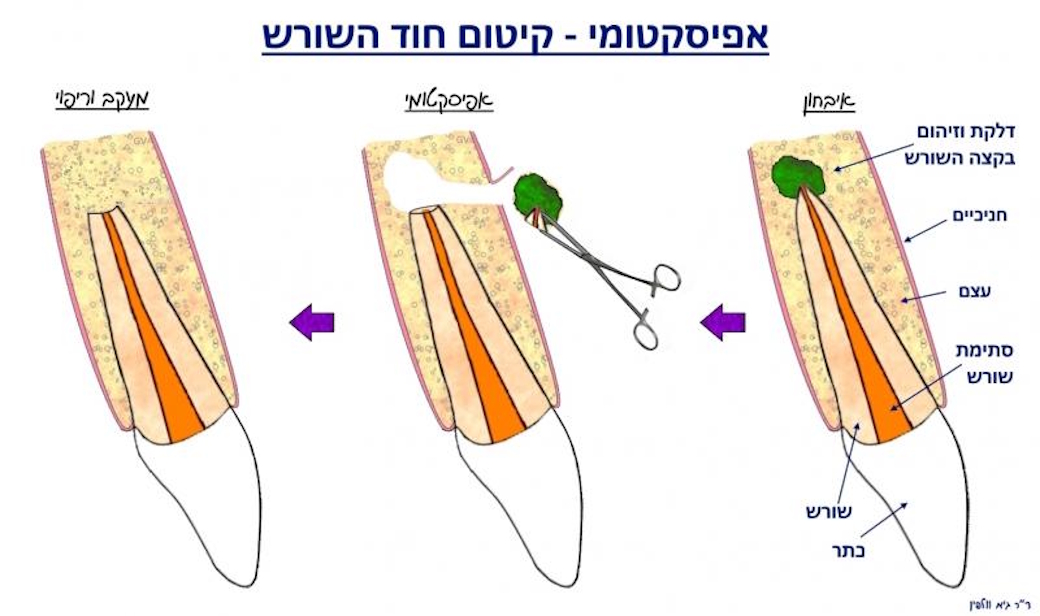

אם בבדיקה רנטגנית מתגלה טיפול שורש לקוי ו/או איזור דלקת סביב שורשי השיניים, על הרופא להסביר את המצב למטופל ולהתריע בפניו על הסכנות הטמונות לשן זו. רגע לפני שעוקרים שן רקובה שהתפתחה בה דלקת בעצב, או שן שסביב טיפול שורש ישן התפתחה דלקת, כדאי לבדוק את האפשרות של הצלת השן, ע"י טיפול שורש או חידוש טיפול שורש. לעיתים אין ברירה ויש צורך בטיפול כירורגי אנדודונטי שנקרא אפיסקטומי, ובו מוסר בצורה כירורגית קצה השורש הדלקתי

דוגמא לאפיסקטומי

(טיפול אנדודונטי כירורגי לקיטום חוד שורש דלקתי) ולסתימה רטרוגרדית